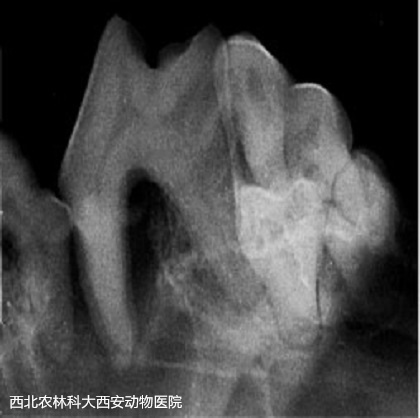

術(shù)前準(zhǔn)備:彈簧開口器撐開口腔,咽部填塞一塊紗布。檢查口腔,可見大量牙結(jié)石見(圖1)。超聲波潔牙術(shù):使用超聲波潔牙器將牙齒的齦上和齦下表面的牙結(jié)石和牙菌斑去除見(圖2)。在潔牙期間發(fā)現(xiàn)其上、下多個(gè)切齒均有松動(dòng),進(jìn)行牙科X線檢查見(圖3),并將上、下切齒各拔掉5顆。108號(hào)齒見(圖4)先前拍片提示存在口鼻瘺,采用注射器噴注可見口腔與鼻腔(右側(cè))連通,使用裂鉆將牙根分開見(圖5),并將牙根分別拔除,口鼻瘺內(nèi)存在多量粘稠惡臭物見(圖6),徹底沖洗口鼻瘺處。牙科手術(shù)刀于上黏膜瓣切出一U形切口,用縫線將黏膜瓣和腭側(cè)黏膜對(duì)合后結(jié)節(jié)縫合見(圖7)。最后,清理口腔去除咽部填塞的紗布?jí)K。術(shù)后通過靜脈輸液給予抗生素和止血藥物。術(shù)后一周每天沖洗口腔兩次,涂抹凝膠四次。一周后回訪恢復(fù)較好,口臭明顯改善,未再出現(xiàn)打噴嚏和流鼻。

圖三

圖四